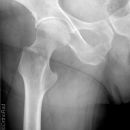

HüftTEP Luxation

Schlecht festgeschraubt